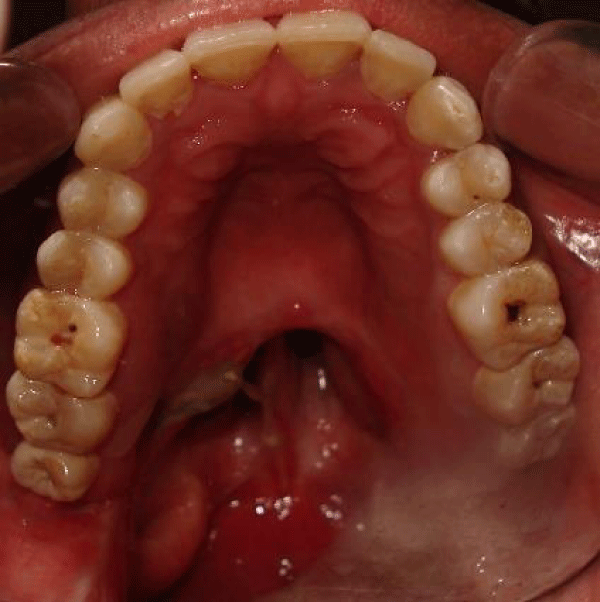

Intaglio surface of Obturator prosthesis.

Intra oral view of resected soft palate. What Is A Palatal Obturator the palatal obturator restores: ️ download dr teeth apps using these links:android users:. Mastication, swallowing, articulation and intelligibility of speech and the contour of. a maxillectomy/ palatectomy prosthesis or obturator restores the surgical defect and aids in the function of speaking, chewing,. a soft palate obturator (also known as a speech and feeding aid/device) replaces the. What Is A Palatal Obturator.